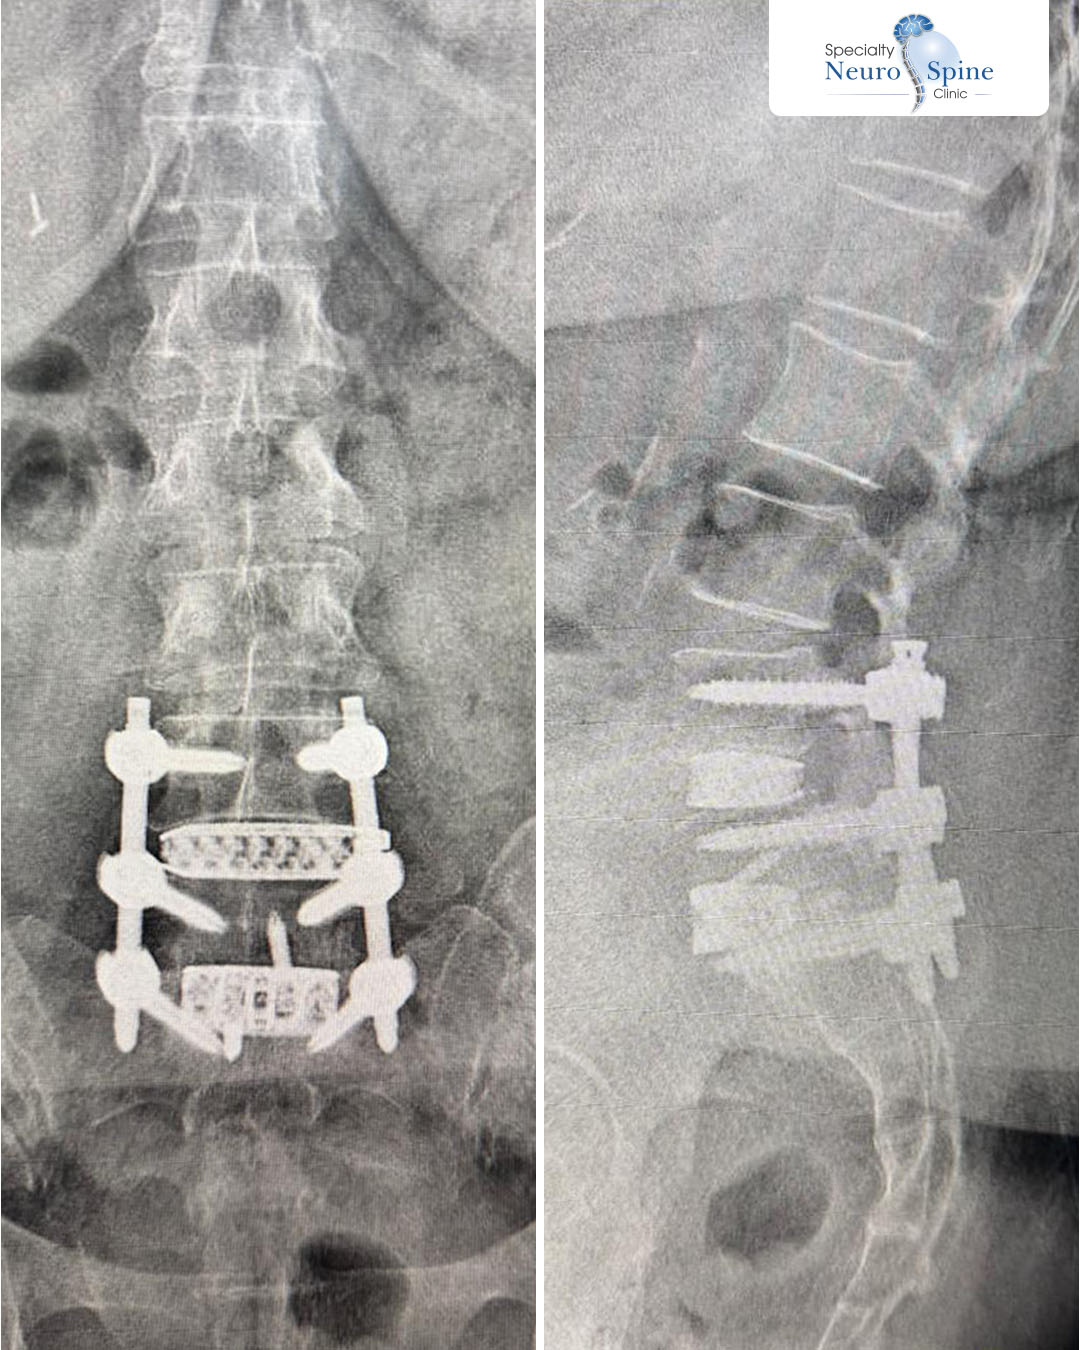

صور الأشعة الأمامية والجانبية لمريضنا الغالي نور، من الحالات المميزة جداً. بعد أن خضع لعملية جراحية قبل 6 أشهر لم تنجح، مما أدى إلى مضاعفات شملت صعوبة الاستلقاء وسقوط القدم.

وبعد معاناة شديدة مع الألم، تمكن الدكتور فراس من إجراء عملية ناجحة لإزالة البراغي القديمة وتثبيت الفقرات باستخدام المنظار.

Oblique Lumbar Interbody Fusion (OLIF)